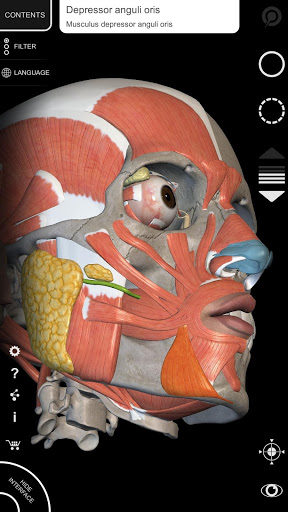

يتيح لك "Anatomy 3D Atlas" دراسة التشريح البشري بطريقة سهلة وتفاعلية.

من خلال واجهة بسيطة وبديهية، من الممكن ملاحظة كل بنية تشريحية من أي زاوية.

تتميز النماذج التشريحية ثلاثية الأبعاد بتفاصيل خاصة ودقة تصل إلى 4K.

يسهل التقسيم حسب المناطق والمناظر المحددة مسبقًا مراقبة ودراسة الأجزاء الفردية أو مجموعات الأنظمة والعلاقات بين الأعضاء المختلفة.

• تصور العضلات من خلال مستويات الطبقات من الطبقات السطحية إلى الأعمق

• من خلال تحديد نموذج أو دبوس، يظهر المصطلح التشريحي ذي الصلة

• وصف العضلات: الأصل والإدخال والتعصيب والعمل